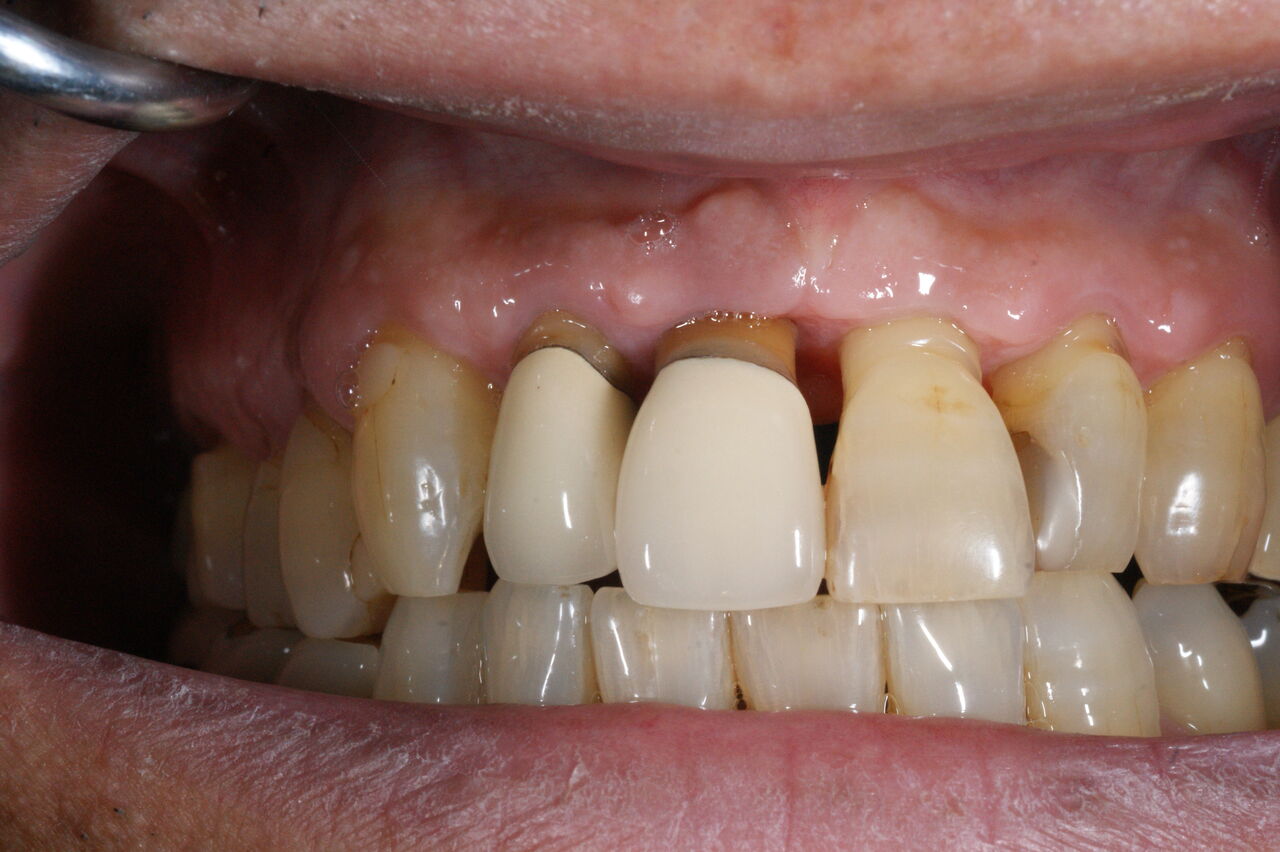

(歯周外科手術時口腔内写真。これ以上の資料は実際に掲載されたブログでご確認下さい!)

前回のブログの概略を説明しますと、患者さんは60歳、男性、会社員、上顎前歯部が普段はなんともないが、時々歯が浮き歯肉が腫れ噛みにくくなるものの、少しするとなおってしまう。

通法にしたがい、初期治療としてブラッシング、スケーリング、ルート プレーニングを行い、再評価したところ、歯周ポケットの深さが残った。浅くするには、原因となっている歯石を除去するための外科処置が必要であることを説明したところ、同意が得られ依頼されたので施行するに至った。

上図は手術時当該部位のデータと縫合時口腔内写真